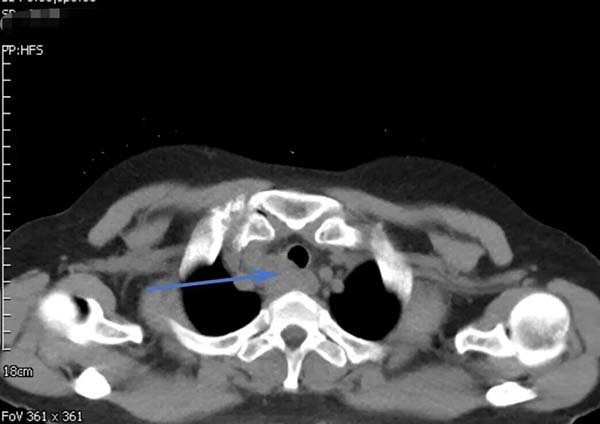

62岁的郑女士近一月来进食时总有食物下咽不畅感,伴有明显哽咽。当地医院胸部增强CT提示食管上段有一约3.7×2.6CM占位性病变,影像报告“不除外食管癌,且可能累及气管后壁”。随后的PET-CT更显示该病灶糖代谢异常增高,代谢活性值高达14.4,强烈指向恶性肿瘤可能。这一系列检查结果让患者及家人陷入焦虑与恐惧。

▲治疗前胸部CT

然而,当通过胃镜直视食管内部时,发现占位隆起更像来自外部压迫,表面光滑。超声胃镜进一步揭示病灶位于食管外,是与食管、气管紧密相邻的不规则低回声区。虽然仍不能排除恶性肿瘤的可能,但病灶位置为诊断带来新的思考。